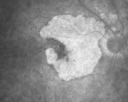

FLUORESCEIN ANGIOGRAPHY: Fluorescein angiography shows concentric geographic atrophy, predominately nasal to the fovea in each eye. The geographic atrophy is unfortunately now closer to the foveal center.